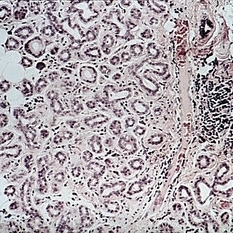

Adenoid cystic carcinoma. A lacrimal gland is seen in the lower right corner. Nests of tumor cells show punched-out areas, giving a "Swiss cheese" appearance (H&E xl6).

Condition/keywords: lacrimal gland